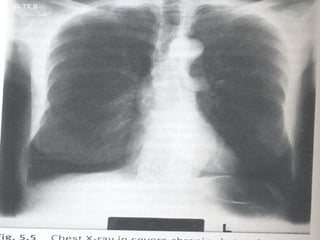

Imagem

Radiografia simples de tórax

- Póstero-anterior

- Perfil

- Apicograma

- Decúbito lateral (raios

horizontais)